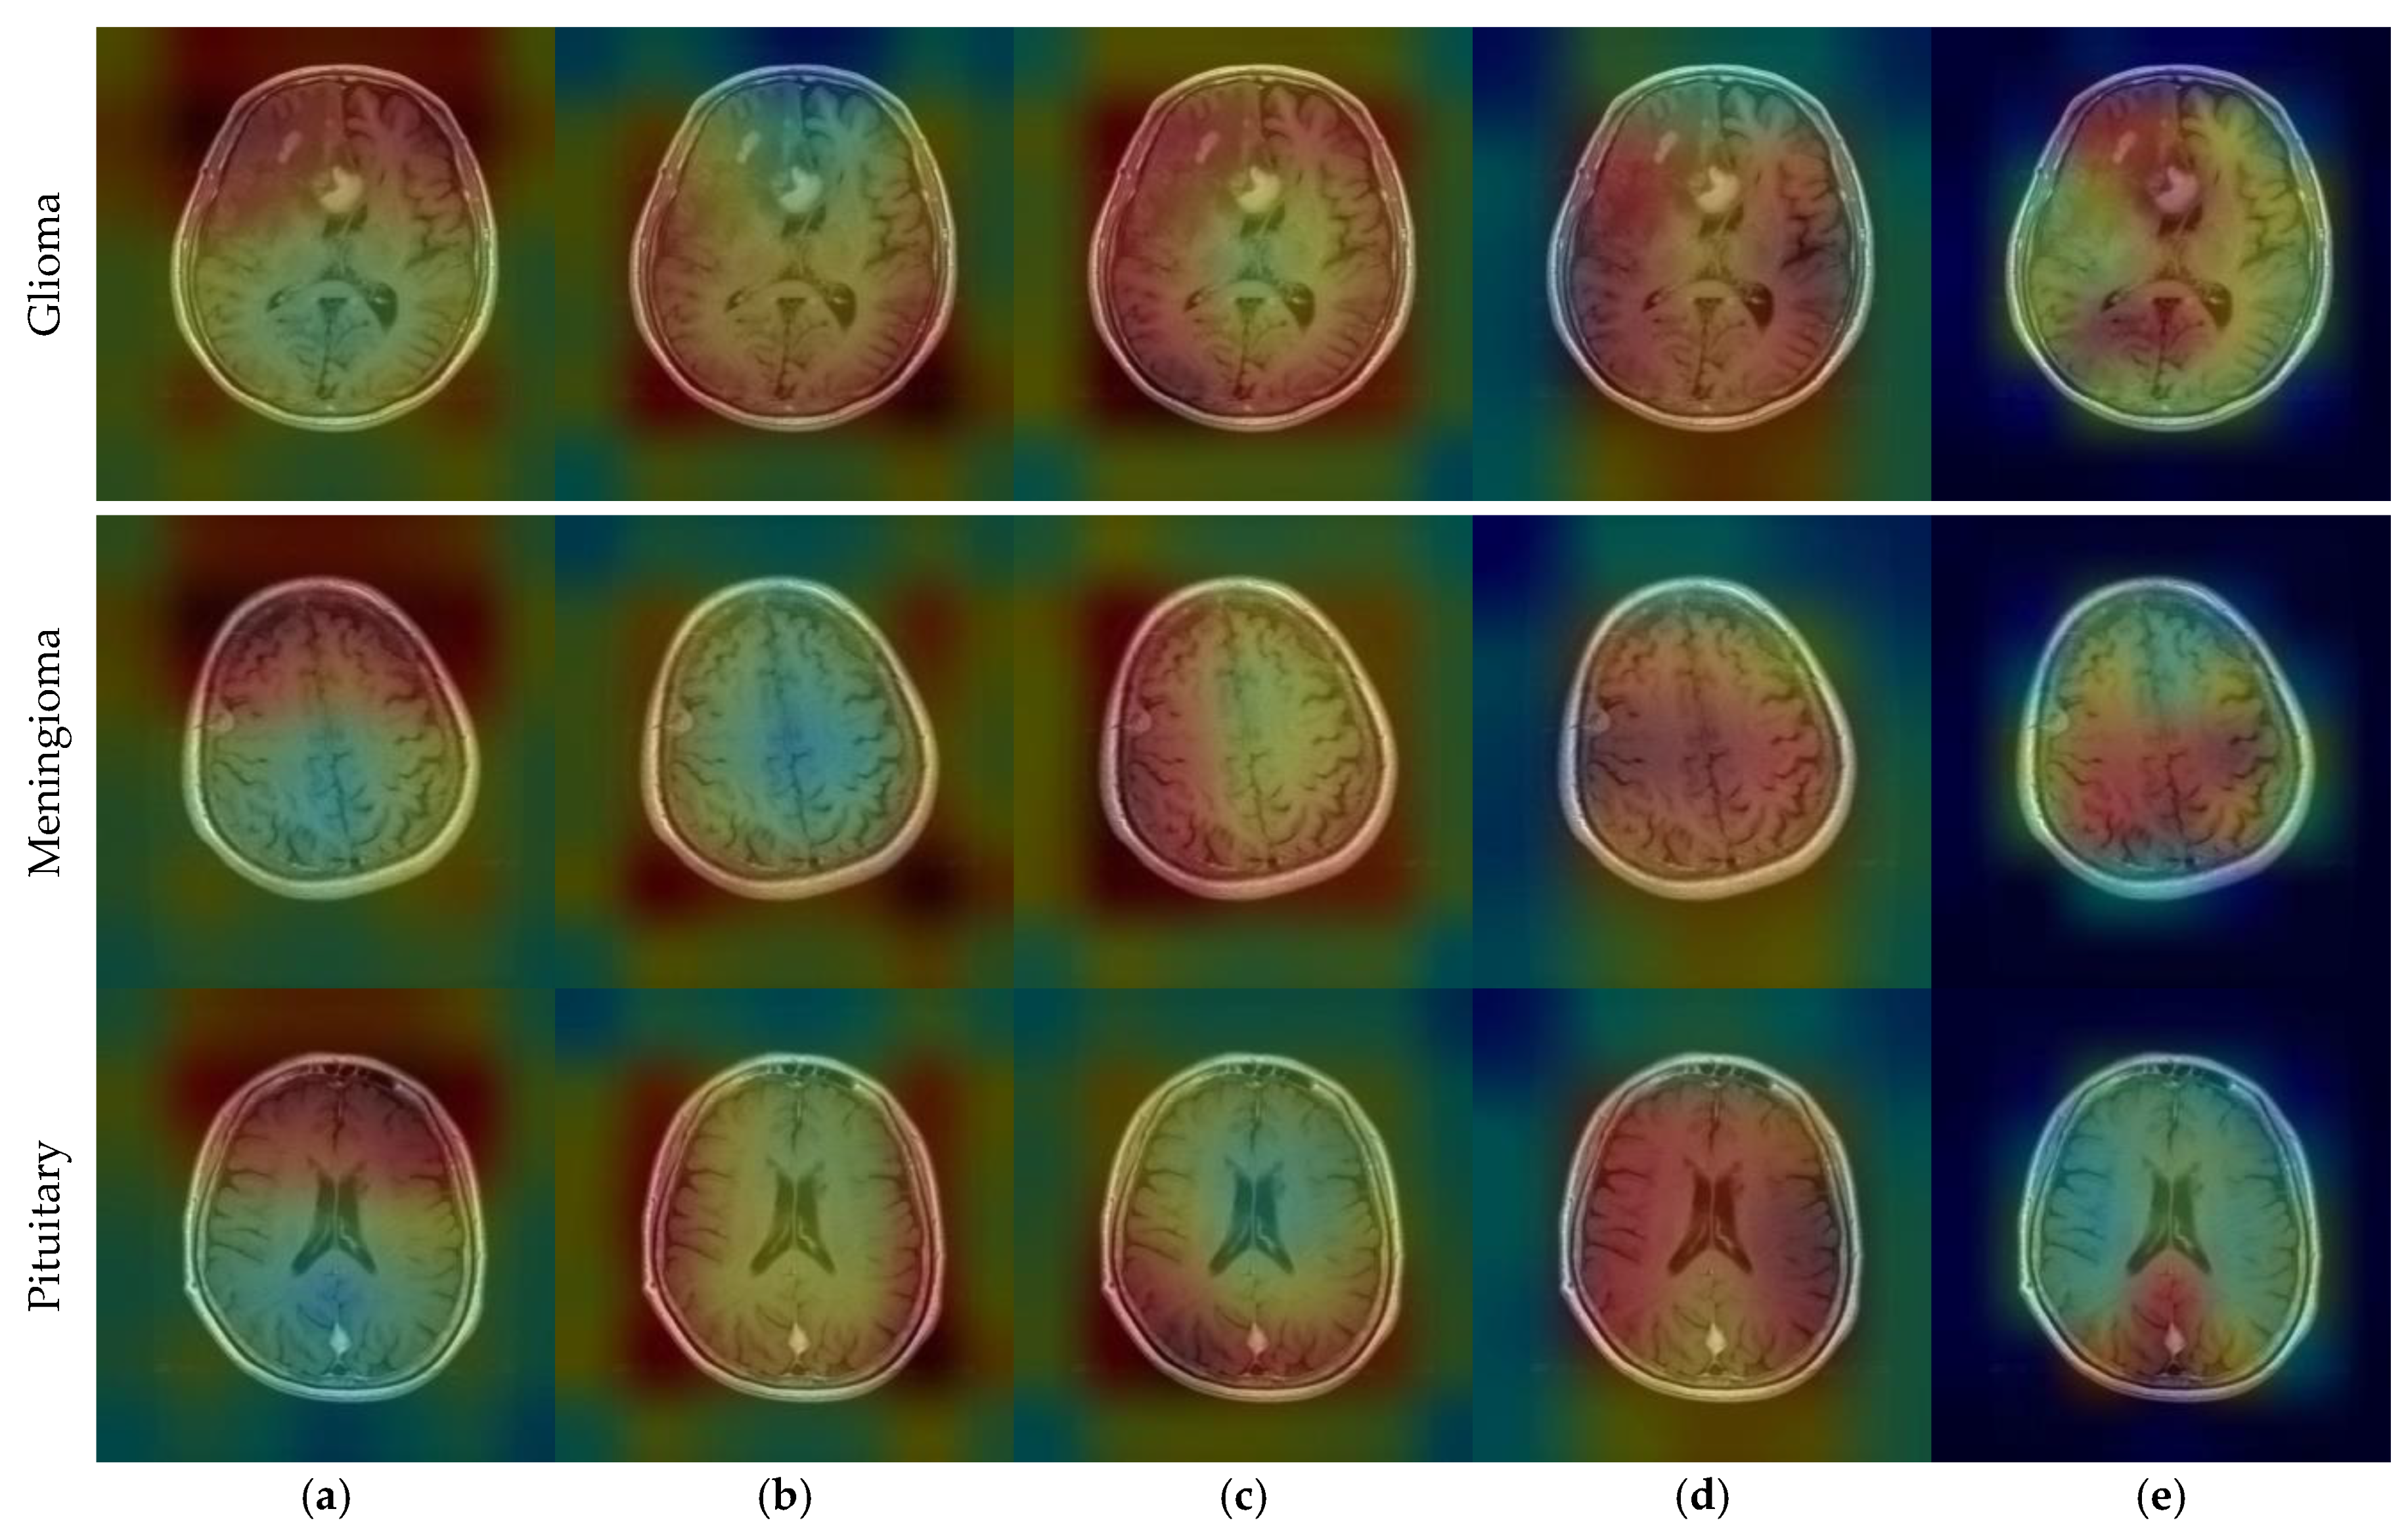

CNN outputs visualized on a heat map with Grad-CAM for Dataset 1, Dataset 2, and Dataset 3 are represented in Figure 10, Figure 11 and Figure 12, respectively. The original images are overlaid with a color spectrum ranging from blue to red, where the red regions indicate the dominant focus during model predictions. The sample images in Figure 1 were used as the original images in the Grad-CAM application. Grad-CAM analyses of the models in the ensemble framework are presented for three data sets. Figure 10 shows that while all models focus on the brain, different models may focus on different regions of the same MRI image. This trend also helps to increase feature diversity. This can be considered an indicator of better performance with ensemble learning.

Figure 10.

CNN outputs visualized on a heat map with Grad-CAM for Dataset 1: (a) DenseNet121, (b) DenseNet201, (c) EfficientNetV2S, (d) ResNet50, and (e) ResNet101.

Figure 11.

CNN outputs visualized on a heat map with Grad-CAM for Dataset 2: (a) DenseNet121, (b) DenseNet169, (c) DenseNet201, (d) InceptionResNetV2, and (e) ResNetRS100.